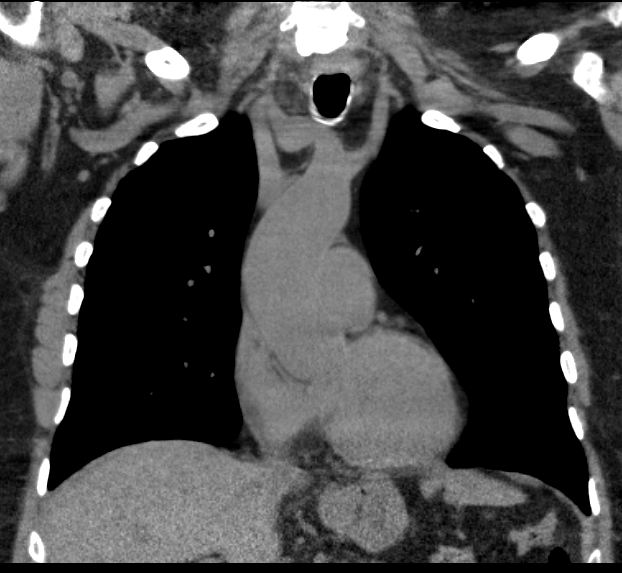

CT Chest/ Abdomen / Pelvis

Lung / bowel / renal primary

Lung metastasis

Lung cancer Renal cell cancer